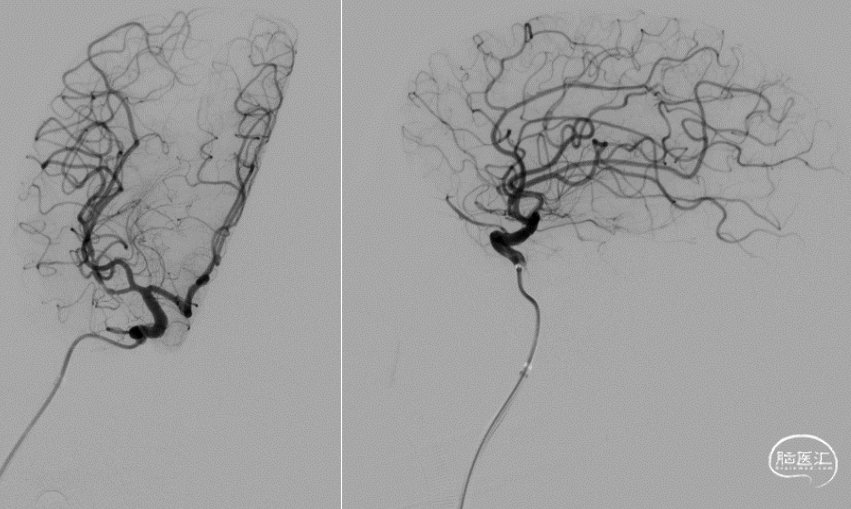

释放3*25mm Syphonet®取栓支架,停留5分钟后撤出Syphonet®取栓支架并保持负压抽吸,第一次复查造影血流未通。

再次重复上述操作,释放Syphonet®取栓支架并停留5分钟后撤出取栓支架并保持负压抽吸,再次复查造影右侧大脑中动脉下干血流恢复,mTICI血流3级。